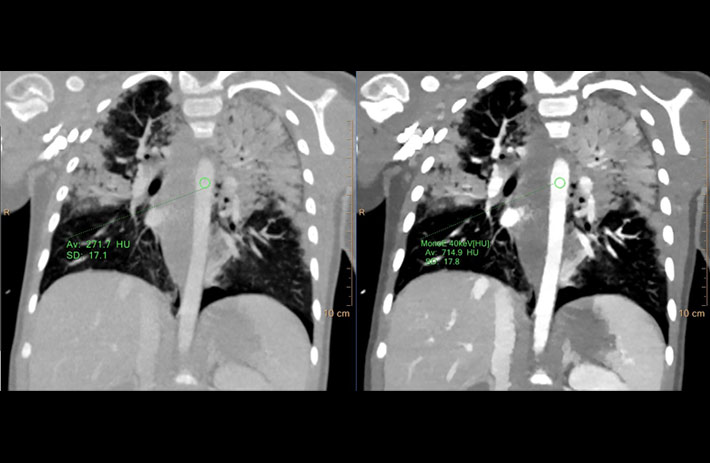

Mit dem Spektral-Detektor-CT werden Spektraldaten automatisch bei jedem Scan erfasst. Die Informationen stehen jederzeit auf der Scankonsole, der CT-Workstation sowie an jedem PACS-Arbeitsplatz zur Verfügung, sodass es nicht notwendig ist, den Patienten erneut zu scannen, bspw. wenn initial zufällige Anomalien festgestellt wurden. Dadurch profitieren Anwender durch eine höhere Diagnosesicherheit und weniger Nachuntersuchungen auf anderen bildgebenden Systemen. Unsere Fallsammlung zeigt, welchen klinischen Mehrwert der Spektral-Detektor-CT in unterschiedlichsten Anwendungsbereichen in der klinischen Routine bringt. Jede Woche gehen neue Fälle live.